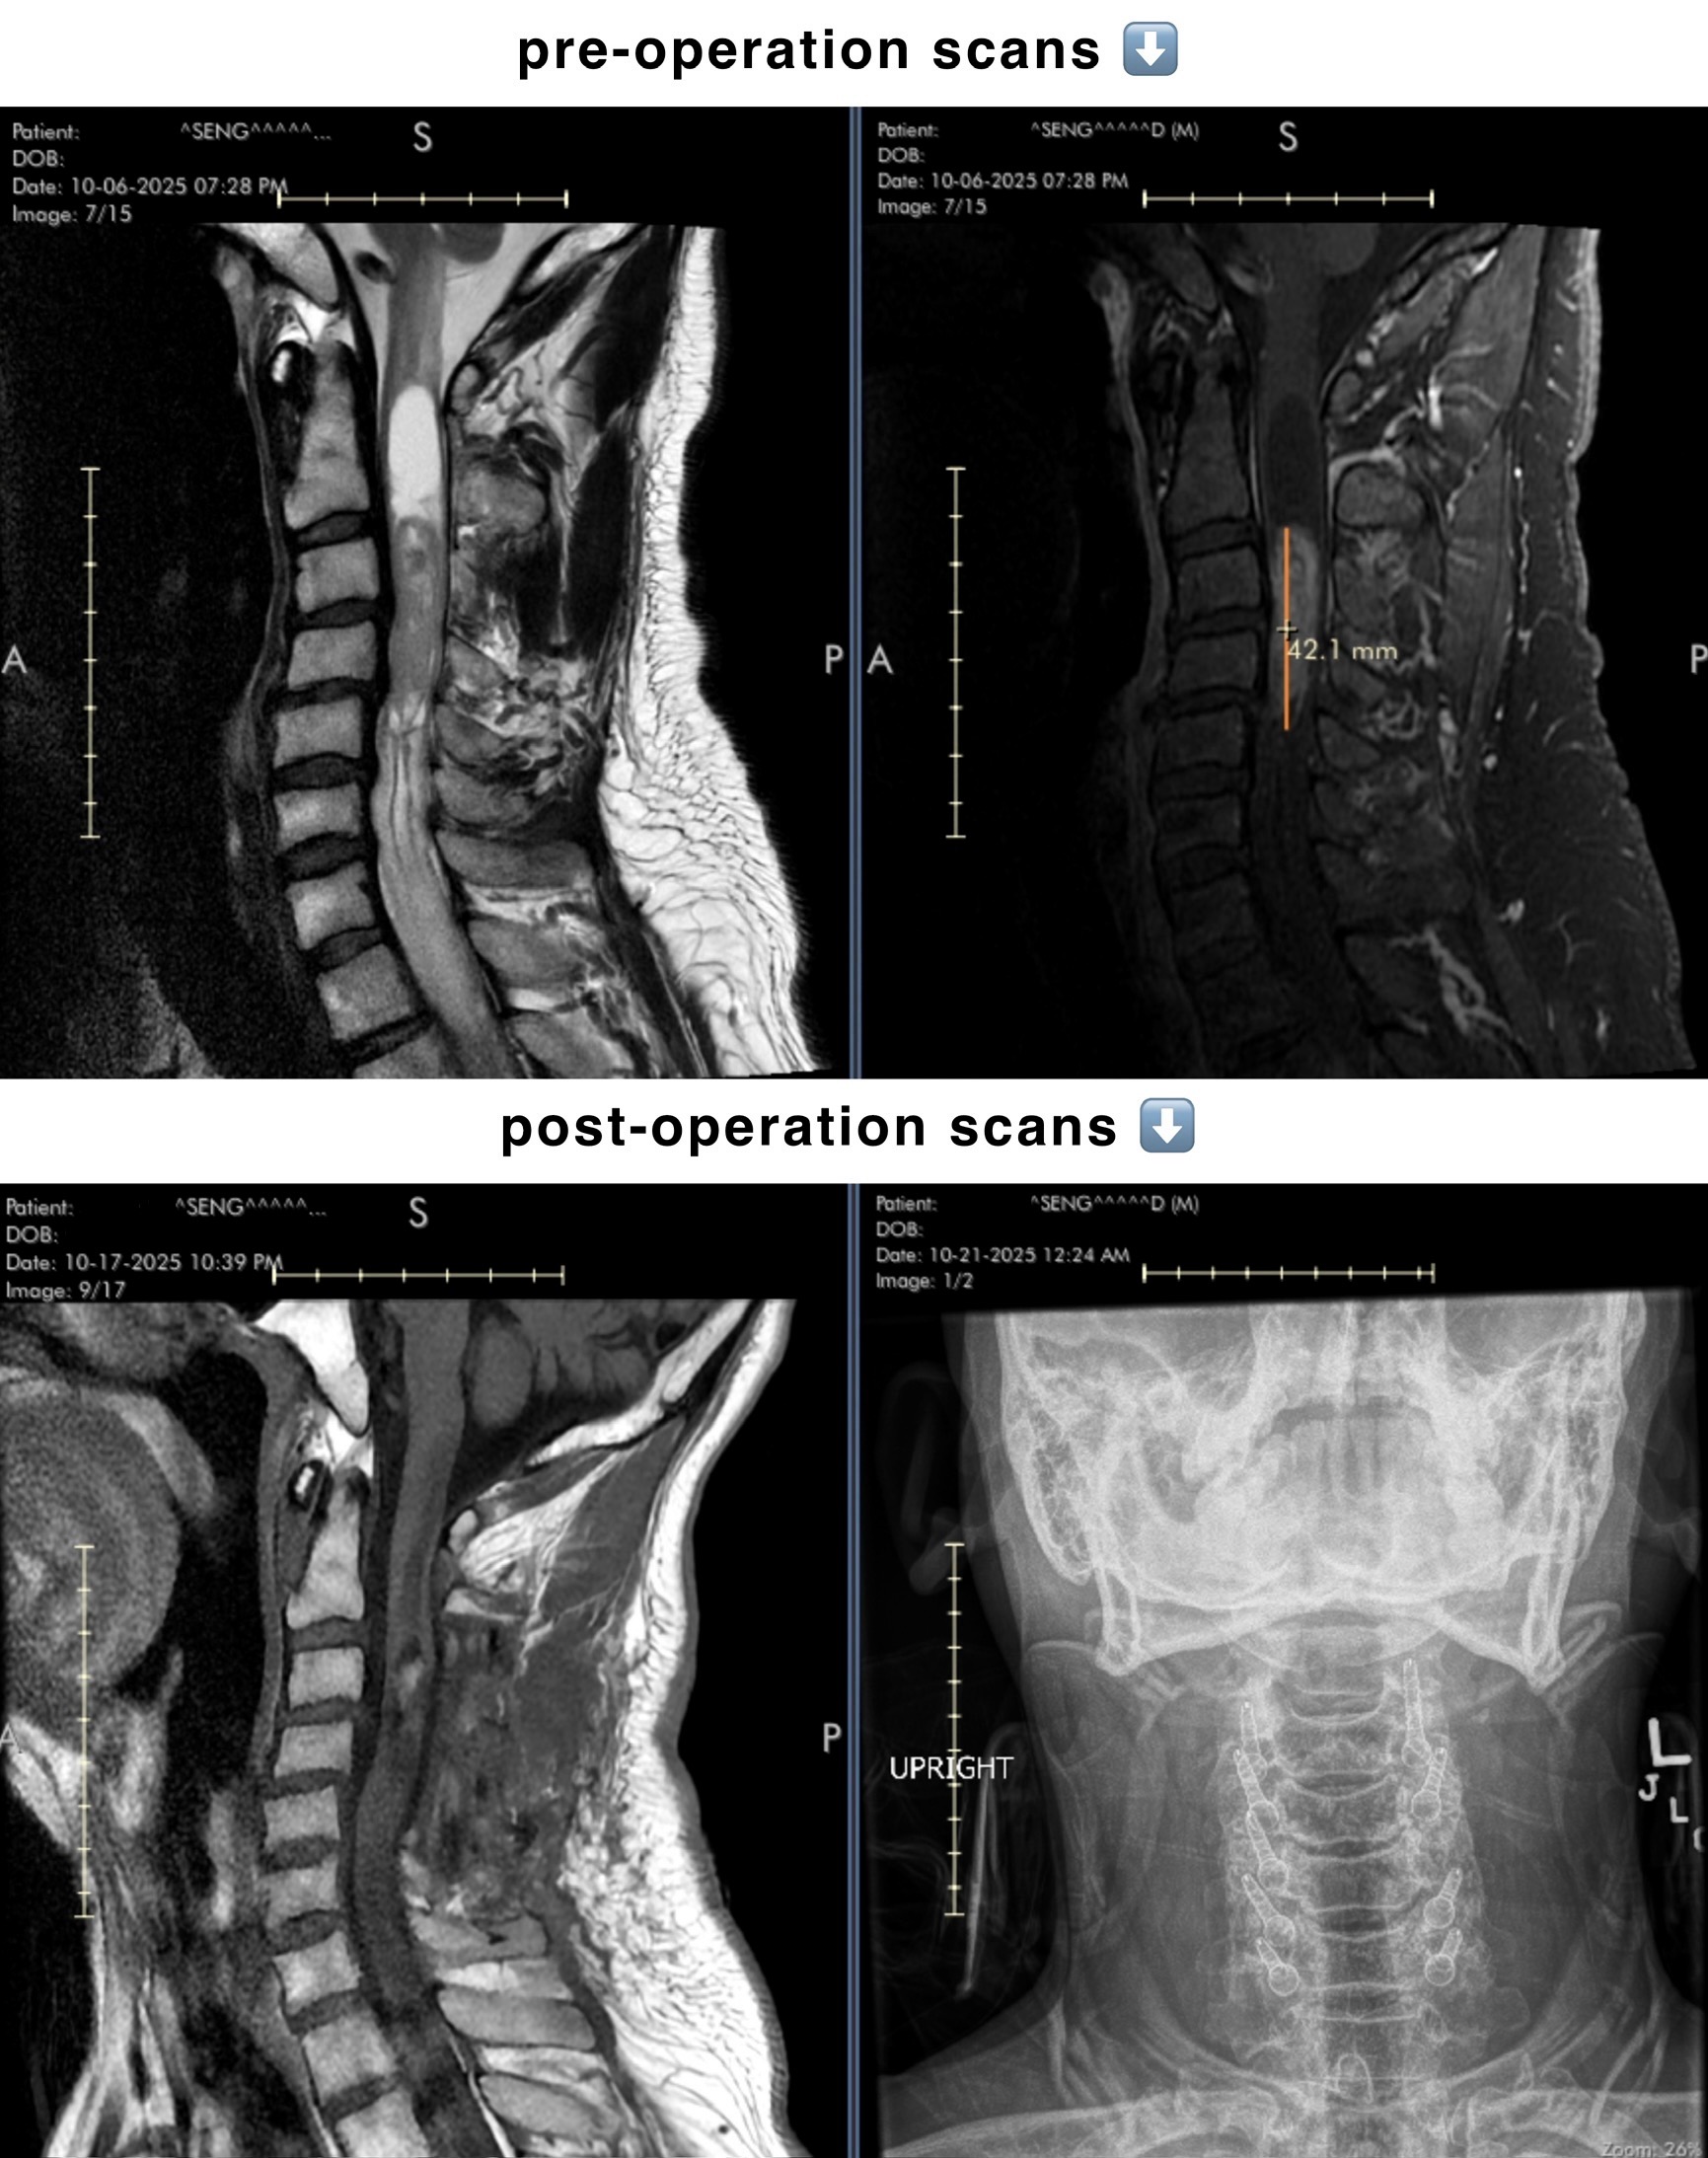

Hello, my name is Amy and I am organizing this fundraiser for my dearest father, Seng, who underwent cervical posterior surgery to remove a grade 2 Ependymoma tumor. I am hoping to raise funds to help cover his medical and rehabilitation costs as well as essential living costs and the rent of our small family restaurant business which has been closed indefinitely until he recovers.

Throughout the two years of going in and out of the emergency room whenever the pain felt too much to bear, doctors were unable to get a diagnosis until recently on the 6th of October when Seng decided to travel three and a half hours from home to Stanford Hospital, desperate to seek a second opinion. At long last, Seng was diagnosed with a spinal Ependymoma tumor–as well as a pituitary tumor–and was promptly admitted for surgery the next week when his condition worsened significantly. Thankfully, the spinal tumor has been removed to a near total recession.

Facing new challenges of having difficulty walking accompanied by loss of feeling in both arms after surgery, Seng is now in the process of rehabilitation under 24-hour care. Not only that, with the rehabilitation center still hours away from home comes the cost of travel expenses and leaving my two younger siblings in my care. My mother, with utter love and dedication, continues to stay by my father’s side, choosing to either sleep in the car or the bedside chair instead for the reason that the cost of lodging is too expensive, only coming home on the weekends to make sure their three children are all well and that bills are being paid. Unfortunately, with the restaurant business being abruptly and indefinitely closed, there is no longer a main source of income for our family of five and we are now struggling to make ends meet.